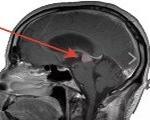

Киста головного мозга у ребенка. Это заполненная жидкостью полость, расположенная в нервной ткани или мозговых оболочках. Возникает при патологиях внутриутробного развития, как следствие ЧМТ, нейроинфекций, инсультов. Заболевание проявляется церебральными симптомами (головная боль, рвота, нарушение сознания) и очаговыми (паралич, снижение чувствительности, нарушения зрения). Для диагностики назначают магнитно-резонансную томографию и компьютерную томографию головного мозга, нейросонографию и ЭЭГ. Лечение кисты рекомендуется при осложненном течении, хирургическим путем с последующей медико-социальной реабилитацией.

• МРТ головного мозга. Магнитно-резонансная томография - «золотой стандарт» диагностики внутричерепных новообразований. Его проводят с контрастированием, так как киста не накапливает краситель, в отличие от злокачественной опухоли. Для лучшей визуализации содержимого полости используется КТ головного мозга.